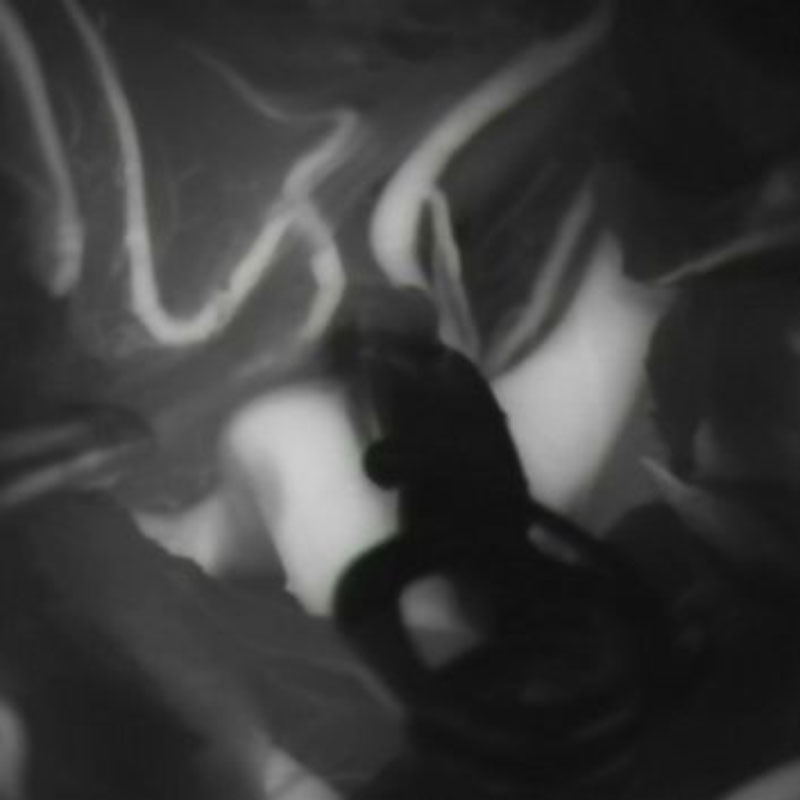

1

'26年1月

40代

右中大脳動脈瘤

クリッピング術

手術前

クリップ前

クリップ後

術後血管撮影